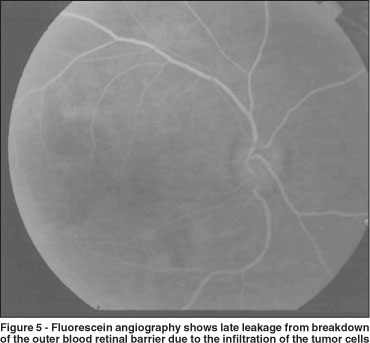

The left eye ocular fundus was normal. Fluorescein angiography (FA) of the patient's right eye revealed first show blocking early because of the mass of tumor cells beneath the RPE. The blocking is especially apparent in the macula where the mass appears to be thickest (Figure 4).

The blocking is of the choroidal fluorescence and because the cells lie in front of the choroid. Then the FA shows late leakage from breakdown of the outer blood retinal barrier, again due to the infiltration of the tumor cells (Figure 5). Fluorescein angiography of the left eye was normal.